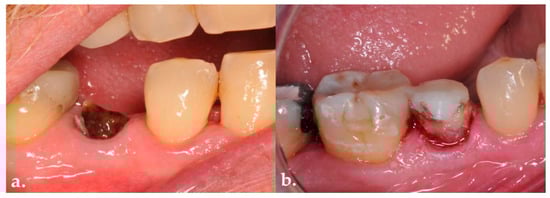

Background: Subcrestally placed implants (SPIs) present advantages for bone preservation and soft tissue support but pose challenges in maintaining peri-implant soft tissue health. This case explores the role of Crest to Restoration Distance (CRD) in the development and resolution of peri-implant mucositis. Case [...] Read more.

Background: Subcrestally placed implants (SPIs) present advantages for bone preservation and soft tissue support but pose challenges in maintaining peri-implant soft tissue health. This case explores the role of Crest to Restoration Distance (CRD) in the development and resolution of peri-implant mucositis. Case Presentation: A 57-year-old woman received two SPIs—one in the upper left and one in the lower right first molar region. Despite similar implant systems and prosthetic protocols, the upper left implant developed mucositis, characterized by bleeding on probing and discomfort, while the lower right implant remained stable. Three-dimensional analysis using cone-beam computed tomography (CBCT) revealed excessive CRD at the affected site. Results: After prosthodontic revision to reduce the CRD, clinical signs of mucositis resolved, with probing depths reduced to less than 1 mm and no bleeding on probing. The control site remained healthy throughout the observation period. Practical Implications: This case highlights CRD as a modifiable prosthetic factor influencing soft tissue stability. A three-zone model—comprising the sulcus, transitional zone (TZ), and subcrestal zone (SZ)—is introduced to provide a biologically grounded framework for understanding soft tissue adaptation around SPIs. Full article

Figure 1